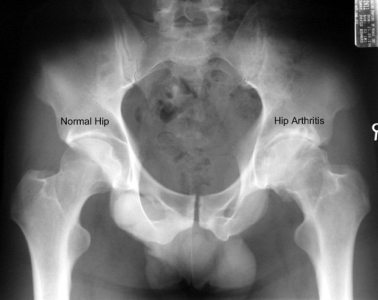

Standing x-rays of the hip joint will give a good assessment of remaining joint space and bone changes related to arthritis:

A simple x-ray should show changes of osteoarthritis. The x-ray findings classically include as joint space narrowing, subarticular sclerosis, osteophytes and degenerative cyst formation.